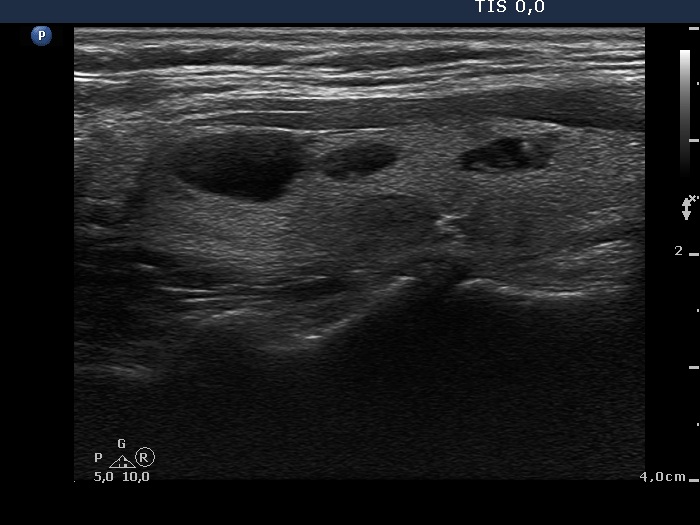

Benign nodular hyperplasia - Case 51. (ultrasonographic picture 2)

Right lobe, longitudinal scan. These are benign-appearing lesions.